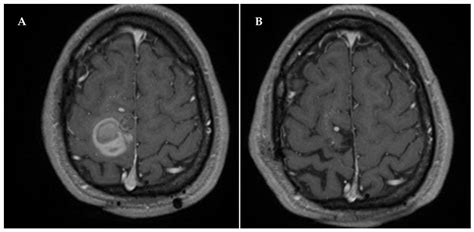

A Developmental Venous Anomaly is essentially a collection of small, radially arranged medullary veins that converge into a single, enlarged central draining vein. This pattern is often referred to in radiological literature as a “caput medusae,” resembling the head of Medusa from Greek mythology. These structures exist to provide venous drainage for healthy brain tissue in regions where the normal deep or superficial venous systems may not have formed correctly during fetal development.

The standard for evaluating a Developmental Venous Anomaly is Magnetic Resonance Imaging (MRI). On T1-weighted images, the DVA may appear as a subtle enhancement, while on T2-weighted or susceptibility-weighted imaging (SWI), the enlarged draining vein becomes very prominent due to the deoxygenated blood flow.

• Contrast administration: Gadolinium is often used to visualize the “caput medusae” pattern clearly.